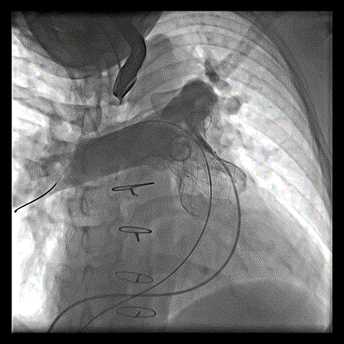

术后造影显示无明显肺动脉瓣反流(左图为患者1,右图为患者2)